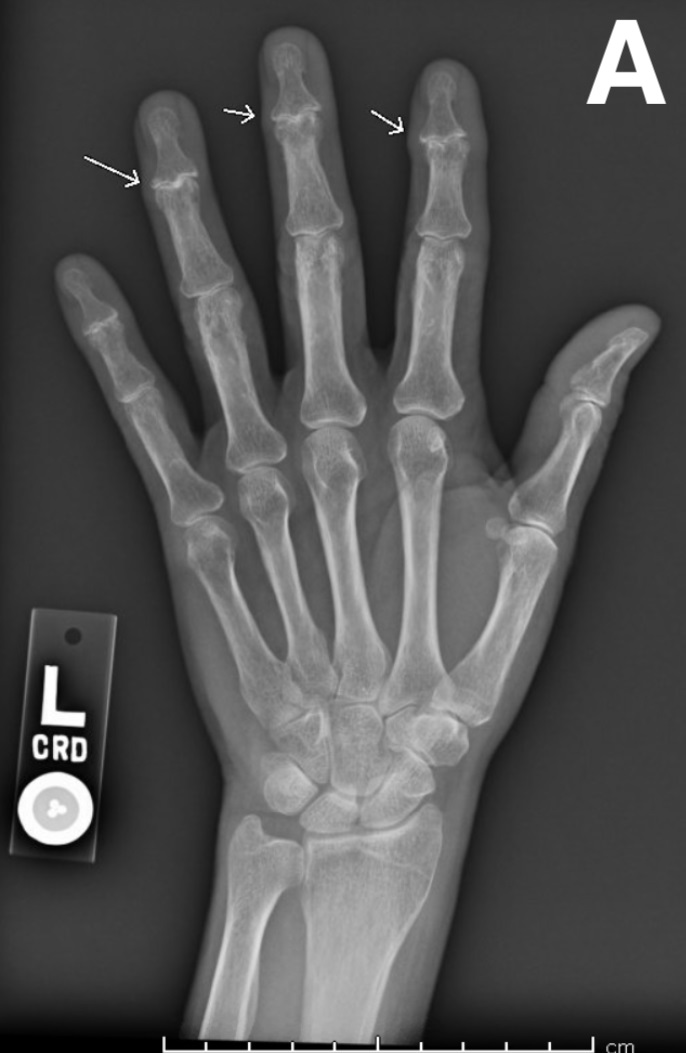

A Woman With Worsening Hand Pain and Stiffness Consultant360 Dip Joint Trauma Dip joint dislocations are very rare injuries and far less common than pip joint dislocations. injuries to the distal interphalangeal (dip) joint, which range from mild sprains to complete ligament ruptures and joint. — phalanx dislocations are common traumatic injury of the hand involving the proximal interphalangeal joint (pip) or distal interphalangeal. Mechanism is typically a hyperextension injury. Dip Joint Trauma.